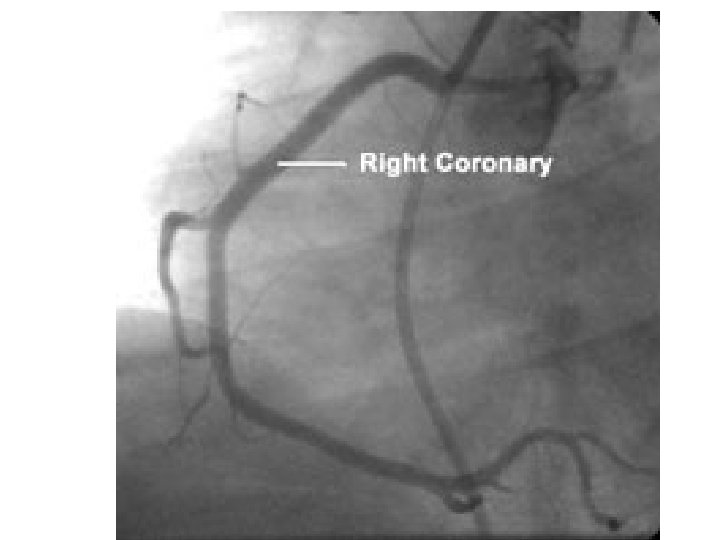

Cardiac catheterization Involve the insertion of plastic catheter within the femoral artery, and progressing the catheter to reach the aorta, the by selecting the coronary artery, dye is injected inside to make the artery visualized on a fluoroscopic screen. Normal flow of the dye indicates normal coronaries, while narrowing or obstruction of the flow indicating ischemic coronary arteries.

Procedure After good skin sterilization insert a plastic catheter percutaneously inside the femoral artery at the groin, then progress the catheter upward under fluoroscopic monitoring until reaching the aortic arch, from that position localizing the coronary arteries should be done, followed by selective insertion of the catheter inside either the left or right coronary artery to inject a dye making the coronary artery more clear to fluoroscopic vision.